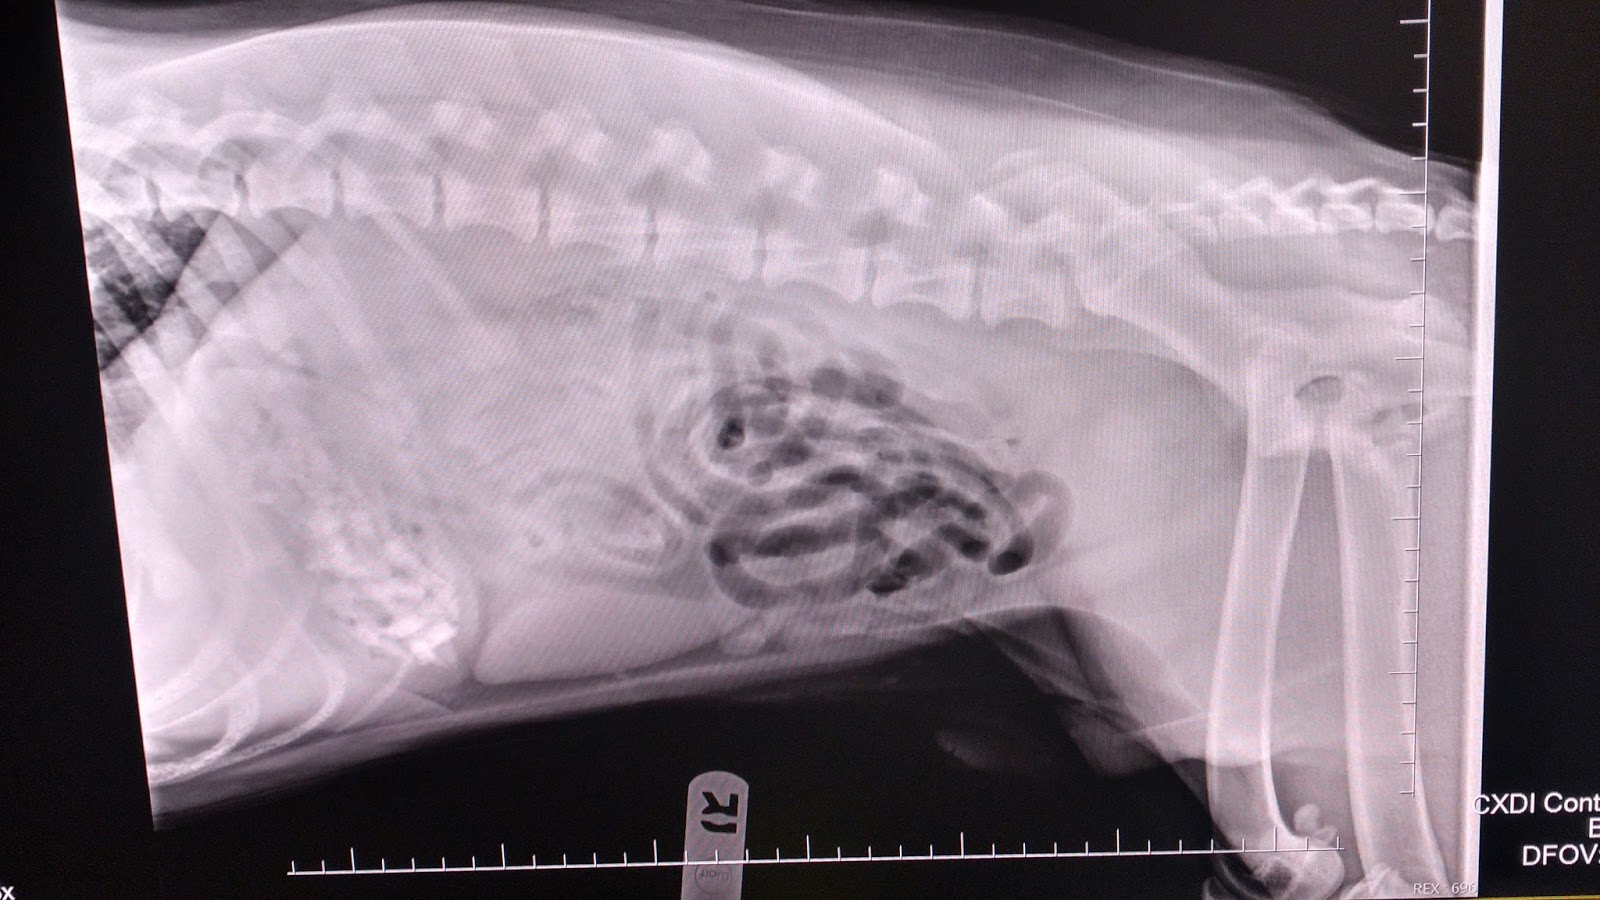

Dog Surgery Operating Stomach to take Stone YouTube How Much Does Surgery Cost To Remove Something From A Dog's Stomach If the object is small and located in the stomach, an endoscope may be able to remove it. The cost of intestinal blockage surgery for dogs can vary dramatically depending on how extensive the surgery is, how long the obstruction has been present,. How much does intestinal blockage surgery cost for a dog? The cost of an endoscopy procedure typically. How Much Does Surgery Cost To Remove Something From A Dog's Stomach.